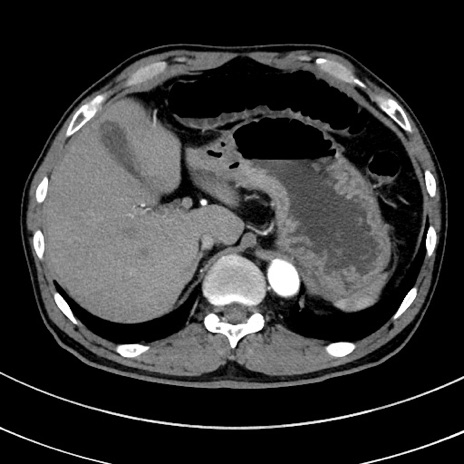

症例8(横断像)

【症例】 60歳代男性

【主訴】 黒色吐物

【現病歴】 4日前から嘔気自覚、2日前の朝食後にも嘔気あり、自分で手で嘔吐反射起こし嘔吐したところ血が混ざっていたため受診。

【既往歴】 5年前汎発性腹膜炎を伴う急性虫垂炎で手術、高血圧、前立腺肥大症、高脂血症

【身体所見】 腹部正中に手術癩痕あり 腹部平坦・軟圧痛なし膨満感あり

【データ】WBC 8400、CRP 4.54